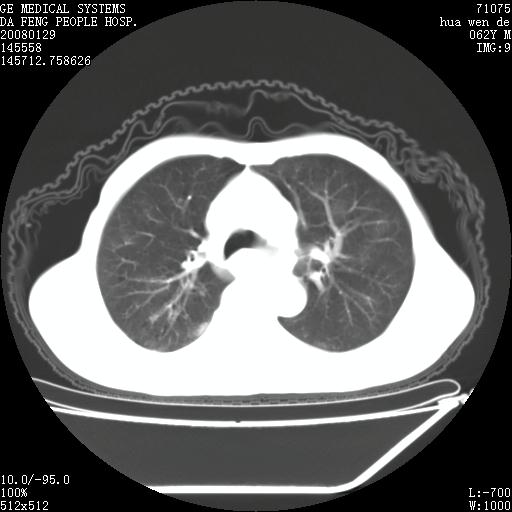

男性,67岁。作肺部检查时发现

胸腔胃并支气管瘘(并发肺炎,肺脓肿形成)

胸腔胃多伴有左侧胸膜术后改变 ,本例不明显

胸腔胃不支持,

因无病史,暂考虑:贲门失驰缓症并肺部化脓感染(吸入性)

胸腔胃多伴有左侧胸膜术后改变~!!请提供病史!!

贲门失驰缓症.肺部感染伴脓肿形成。支持!是否吸入性要结合临床诊断,我们影像是看不出来的。但胸腔胃能排除(1.没有手术史支持,2.双侧胸廓对称,胸壁、肋骨及胸膜规整,3,食管壁明显扩张内壁光滑,胸腔胃黏膜皱襞多较厚)。

作者: zsl6918 时间: 2008-1-31 05:15

贲门失驰缓症.(硬皮病?)肺部感染考虑结核